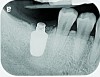

Fig 13. Radiograph depicting peri-implantitis.

Figure 13